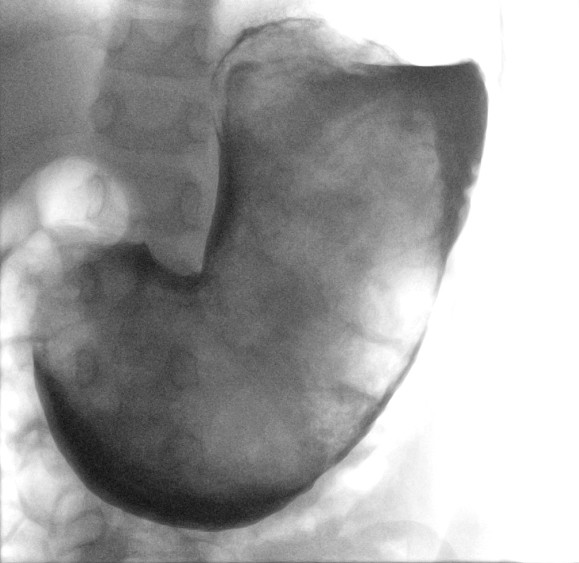

Dette ble bekreftet ved laparotomi samme dag. Man fjernet en trikobesoar som fylte hele magesekken, med en ca. 60 cm lang utløper som ble trukket retrograd opp fra tynntarmen (figur 2). Trikobesoaren veide over 750 g. Det postoperative forløpet var ukomplisert, og pasienten ble utskrevet femte postoperative dag med avtale om videre barnepsykiatrisk oppfølging.

Som det framgår av figur 2, var hoveddelen av besoaren over 20 cm lang og største diameter om lag 10 cm. Den beholdt form som magesekken etter fjerning. Dette skyltes at den var svært kompakt, og den ville ikke ha egnet seg for endoskopisk fjerning, som ofte viser seg å ikke være vellykket (2). Laparotomi med gastrotomi anbefales ved fjerning av store trikobesoarer i magesekken (2).

Trikobesoaren hadde en 60 cm lang hale (figur 2). Den var palpabel et godt stykke ned i jejunum og lot seg fjerne ved forsiktig traksjon gjennom åpningen i magesekken. Dersom dette ikke hadde latt seg gjøre, måtte man ha fjernet utløperen gjennom en separat åpning av tynntarmen for å hindre at den kilte seg fast og forårsaket tarmobstruksjon (2). En slik hale forekommer i et fåtall av tilfellene (4, 8), men har på grunn av det karakteristiske utseendet blitt kjent under et eget navn i medisinsk litteratur, Rapunsels syndrom (2, 4, 6). Navnet henspiller på den lange hårmanken til Rapunsel som var fanget i tårnet, kjent fra brødrene Grimms eventyrsamling fra 1812.